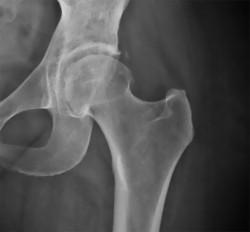

Como criterio de inclusión se ha tenido en cuenta toda artroscopia de cadera realizada en ese periodo de tiempo, que haya sido tratada por un CFA y que tuviese un control radiológico preoperatorio y postoperatorio con un mínimo de 2 meses tras la cirugía. Los pacientes han sido intervenidos mediante técnica fuera-dentro, con tracción de la extremidad para la fase acetabular. En su mayoría han sido pacientes tratados por un CFA de carácter mixto, con lesión labral. En caso de presencia de calcificación, tal y como se ha realizado en otros estudios, la hemos clasificado según la clasificación de Brooker para CH (Figura 1).

Figura 1. Radiografía anteroposterior de cadera. Control a los 3 meses de la cirugía con presencia de calcificación heterotópica (Brooker I).